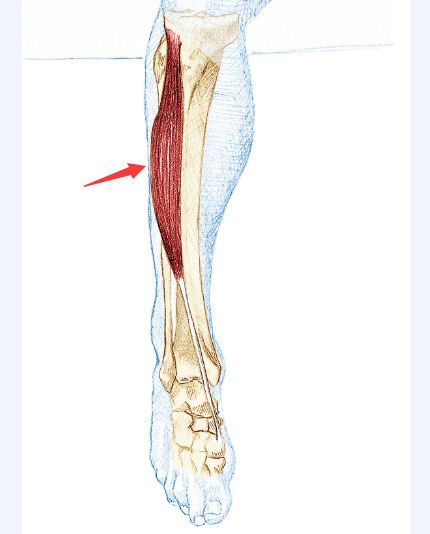

胫骨前肌紧绷

胫骨前肌位于小腿前侧和胫骨外侧。它起于腓骨的整个前侧,经过脚踝和足部顶部,与大脚趾相连。胫骨前肌的功能是收缩踝关节,内翻足部(旋后)。

如果快步行走时无法适应这种强度,胫骨前肌就可能出现紧绷。肌肉在跑步或骑踏板上有脚扣的自行车时也会紧绷。